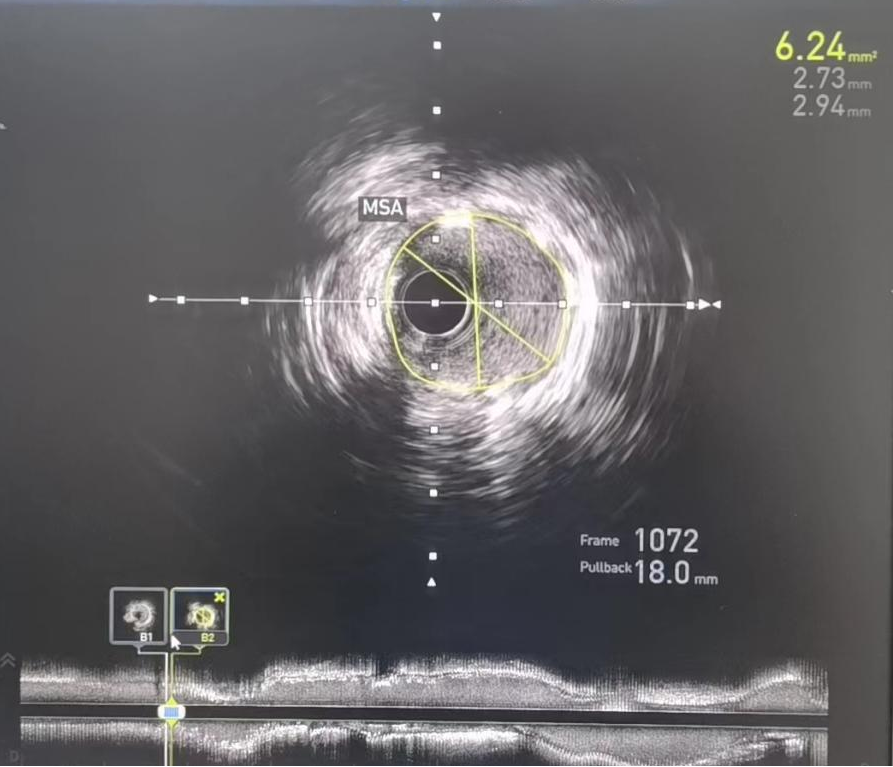

术前:IVUS-前降支管腔中段严重狭窄,最小管腔面积仅2.64mm2

术后:IVUS-前降支支架植入后

IVUS检查提示右冠中段支架以远病变加重,右冠原支架管腔畅通,经IVUS测量得出病变处MLA(管腔最小横截面积)2.64mm2,结合心电图缺血判断,该病变为患者心绞痛发作罪犯病变,对病变处实施介入治疗。